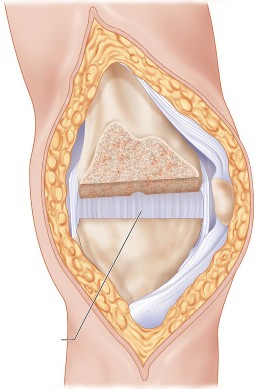

مفصل الركبة هو أحد أكبر وأعقد المفاصل في جسم الإنسان، وهو ضروري للحركة اليومية مثل المشي والجري والقفز والانحناء. يتكون هذا المفصل من التقاء ثلاث عظام رئيسية:

- عظم الفخذ (Femur): وهو العظم الأطول في الجسم، يشكل الجزء العلوي من المفصل.

- عظم الساق (Tibia): وهو العظم الرئيسي في الجزء السفلي من الساق، يشكل الجزء السفلي من المفصل.

- الرضفة (Patella): وهي عظمة صغيرة مثلثة الشكل، تُعرف أيضًا باسم "صابونة الركبة"، تقع أمام المفصل لحمايته وتسهيل حركة الأوتار.

تُغطى نهايات هذه العظام بغضروف مفصلي أملس ومرن (غضروف زجاجي)، يسمح للعظام بالانزلاق بسلاسة فوق بعضها البعض دون احتكاك، ويمتص الصدمات. يوجد أيضًا غضروفان هلاليان (Menisci) على شكل حرف C بين عظم الفخذ وعظم الساق، يعملان كممتصات صدمات إضافية ويزيدان من استقرار المفصل.

يُحاط المفصل بمحفظة مفصلية تحتوي على سائل زليلي (Synovial Fluid) يغذي الغضروف ويزيت المفصل. تُعزز استقرار الركبة بواسطة شبكة قوية من الأربطة:

الانحراف التقوسي، المعروف أيضًا بـ "تقوس الساقين" أو "الركبة المقوسة"، هو حالة تتميز بوجود زاوية غير طبيعية في مفصل الركبة، حيث تتجه الركبة نحو الخارج بينما تتجه الكاحلين نحو الداخل عند الوقوف معًا. هذا يعني أن الساقين تبدوان مقوستين إلى الخارج، مما يضع ضغطًا مفرطًا على الجزء الداخلي (الإنسي) من مفصل الركبة.

في الركبة الطبيعية، يمر خط وزن الجسم بشكل متساوٍ تقريبًا عبر مركز المفصل. أما في الركبة التقوسية، فإن هذا الخط ينحرف نحو الجانب الإنسي، مما يؤدي إلى:

- زيادة الضغط على الغضروف الإنسي: يتسبب هذا الضغط المستمر في تآكل الغضروف في الجزء الداخلي من الركبة بشكل أسرع بكثير من الجزء الخارجي.

- تضييق المسافة المفصلية الإنسية: مع تآكل الغضروف، تقل المسافة بين عظم الفخذ وعظم الساق في الجانب الداخلي، مما يزيد من الاحتكاك والألم.

- تلف الأنسجة الرخوة: يمكن أن يؤثر الضغط غير المتوازن على الأربطة والأنسجة المحيطة، مما يزيد من عدم الاستقرار.

يُعد الانحراف التقوسي مشكلة شائعة وقد يكون خلقيًا (موجودًا منذ الولادة)، ولكنه غالبًا ما يتطور بمرور الوقت نتيجة لخشونة الركبة المتقدمة، حيث يؤدي التآكل غير المتساوي للغضروف إلى تفاقم التشوه. تصحيح هذا الانحراف هو جوهر جراحة استبدال مفصل الركبة التقوسي، وهو ما يتقنه الأستاذ الدكتور محمد هطيف لضمان استقرار المفصل وطول عمره.